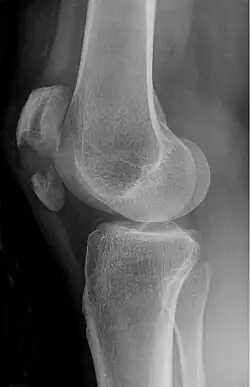

Some people have a normal bipartite patella or two-part patella which can appear as a fracture. The fragment is usually seen in the top outer corner of the patella and can be distinguished from a fracture by being present in both knees.[6]